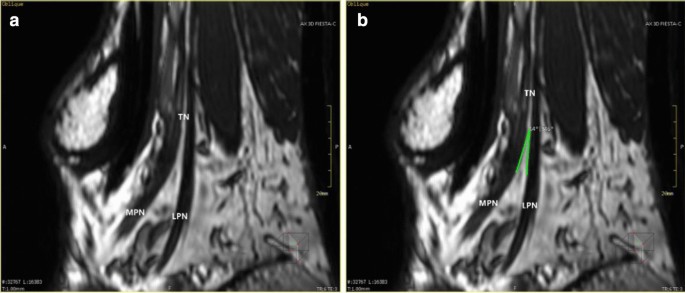

Image reformation method

MPR shows the bifurcation of the medial and lateral plantar nerves at the same plane and bifurcation angle measurement: a the image of the oblique sagittal plane shows the bifurcation of the tibial nerve, the medial and lateral nerves of the plantar; b the angle between the medial and lateral nerves of the plantar can be measured on the oblique plane passing through the bifurcation of the tibial nerve

The reformation image of the medial and lateral plantar nerve was uniform in thickness and tapering from near to far, and the display range was obviously larger than that of the two at the same time, but when the two were displayed at the same time, the bifurcation position and morphology could be defined. The angle of the medial and lateral plantar nerves ranged between 6° and 35°, as shown in Fig. 7.